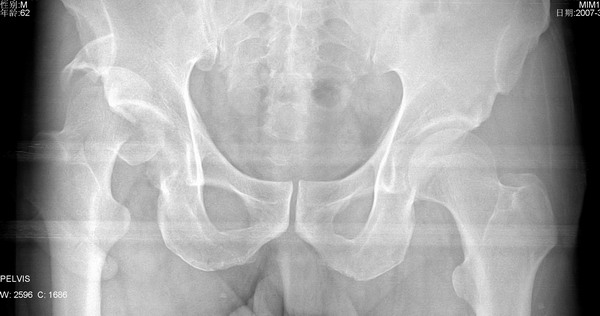

以下是引用dyqct在2007-3-10 15:56:00的发言:[br]骨折。[br][br][br][br]